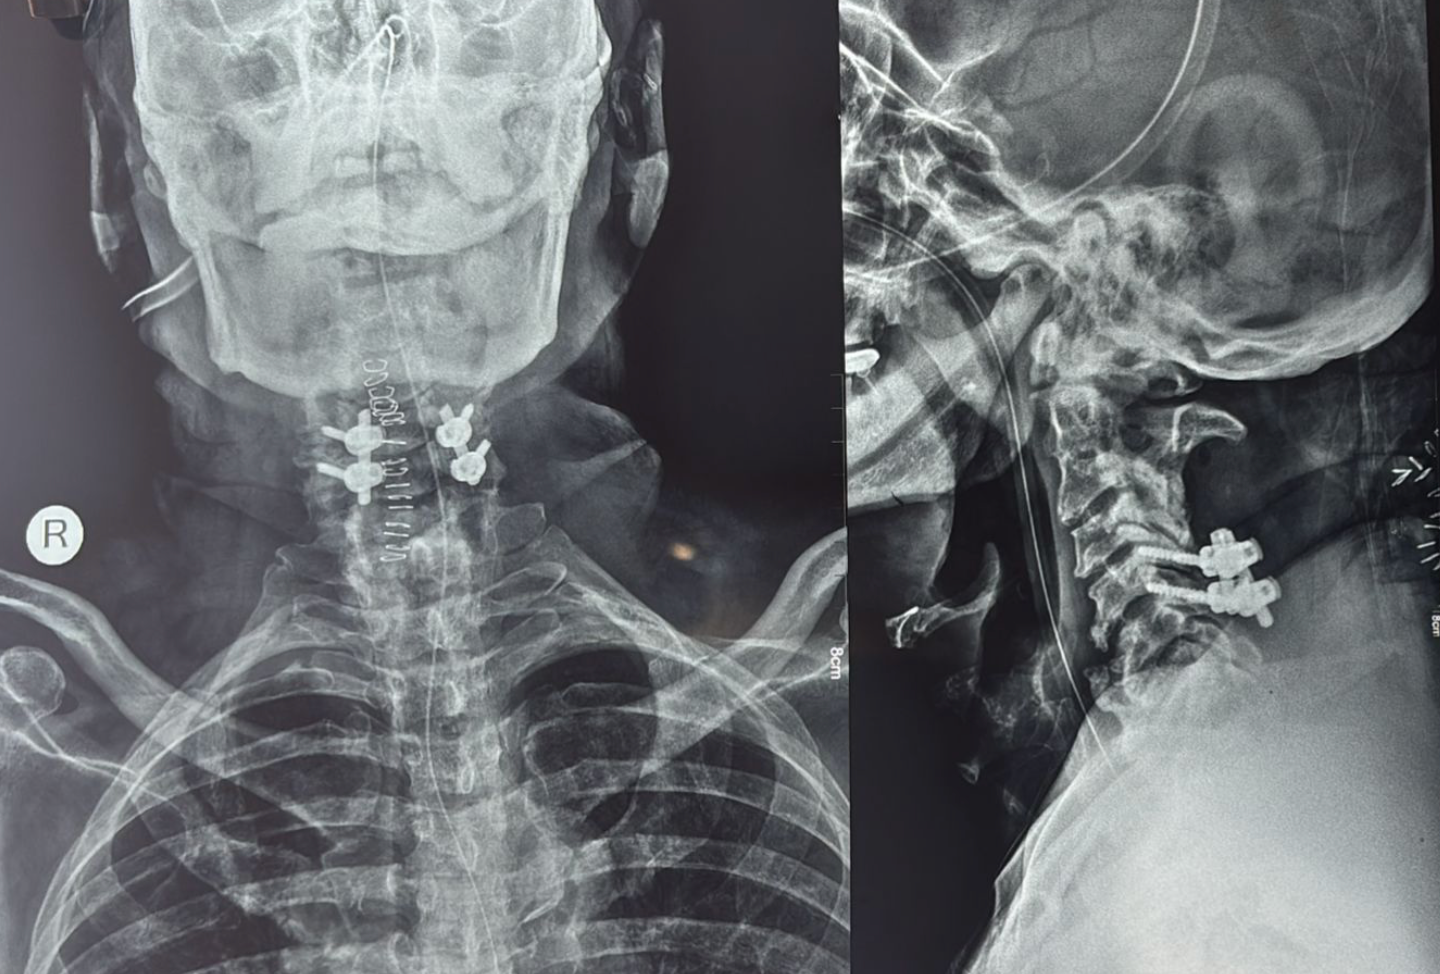

- X-rays: To evaluate alignment, instability, and degenerative changes

- Anterior Cervical Discectomy and Fusion (ACDF)

- Cervical Corpectomy

- Posterior decompression (Laminoplasty / Laminectomy with fusion)

The choice of surgery depends on the number of levels involved, spinal alignment, and cause of compression.